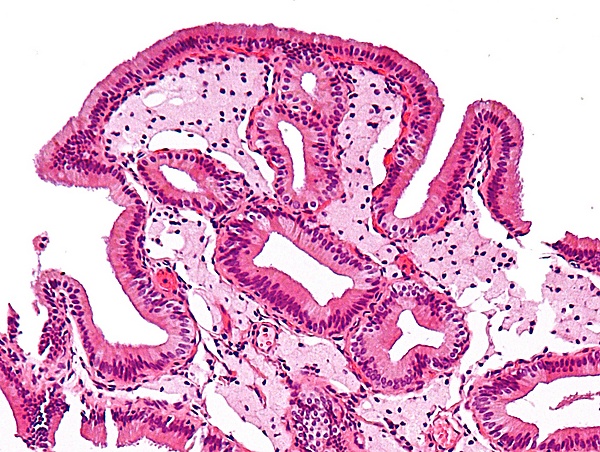

Механизм развития холестероза желчного пузыря исследован достаточно хорошо. Липиды, откладывающиеся в стенке органа, поступают из видоизменённых липопротеинов низкой плотности, отличающихся изменениями в структуре аполипопротеинов. Вследствие этих преобразований липопротеины получают способность связываться с рецепторами макрофагов. Подвергшиеся модификации липопротеины легче проникают внутрь стенки желчного пузыря, поглощаются макрофагами и образуют пенистые клетки. Внешне скопление пенистых клеток на верхушке ворсин выглядит как жёлтые пятна на внутренней оболочке желчного пузыря[5].

Проводится гистологическое исследование желчного пузыря после холецистэктомии. При котором обнаруживают пенистые клетки или отдельные их скопления в слизистой оболочке и подслизистом слое желчного пузыря, а также признаки дистрофии эпителия[5].